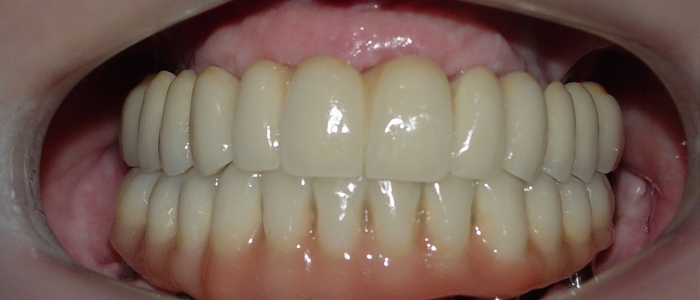

Próteses Fixas Definitivas em Porcelana, em 2013 - Clínica Cliniface

Próteses Fixas Definitivas em Porcelana, em 2013

Imagem Próteses Fixas Definitivas Superior e Inferior, em 2013 - Clínica Cliniface

Imagem Próteses Fixas Definitivas Superior e Inferior, em 2013